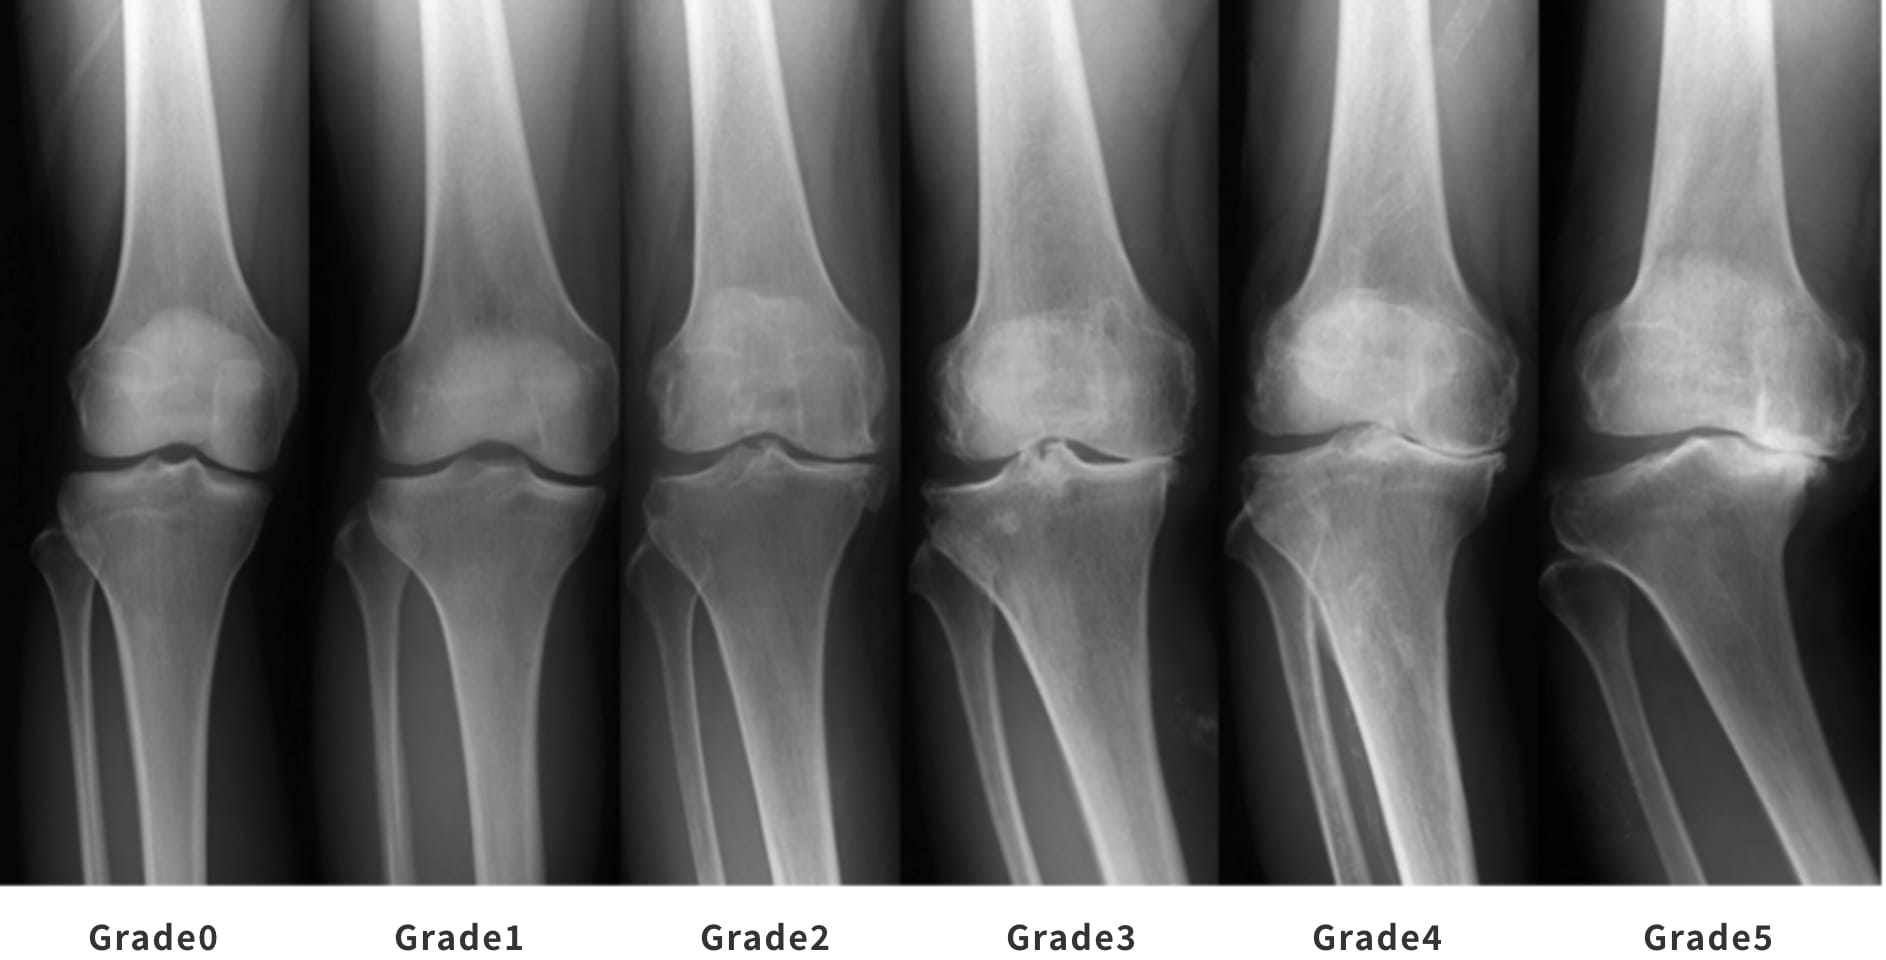

各プログラムには独自の要件と申請プロセスがあります。 OAの重症度を示す医療記録または医療画像のコピーを必要とする場合もあります。